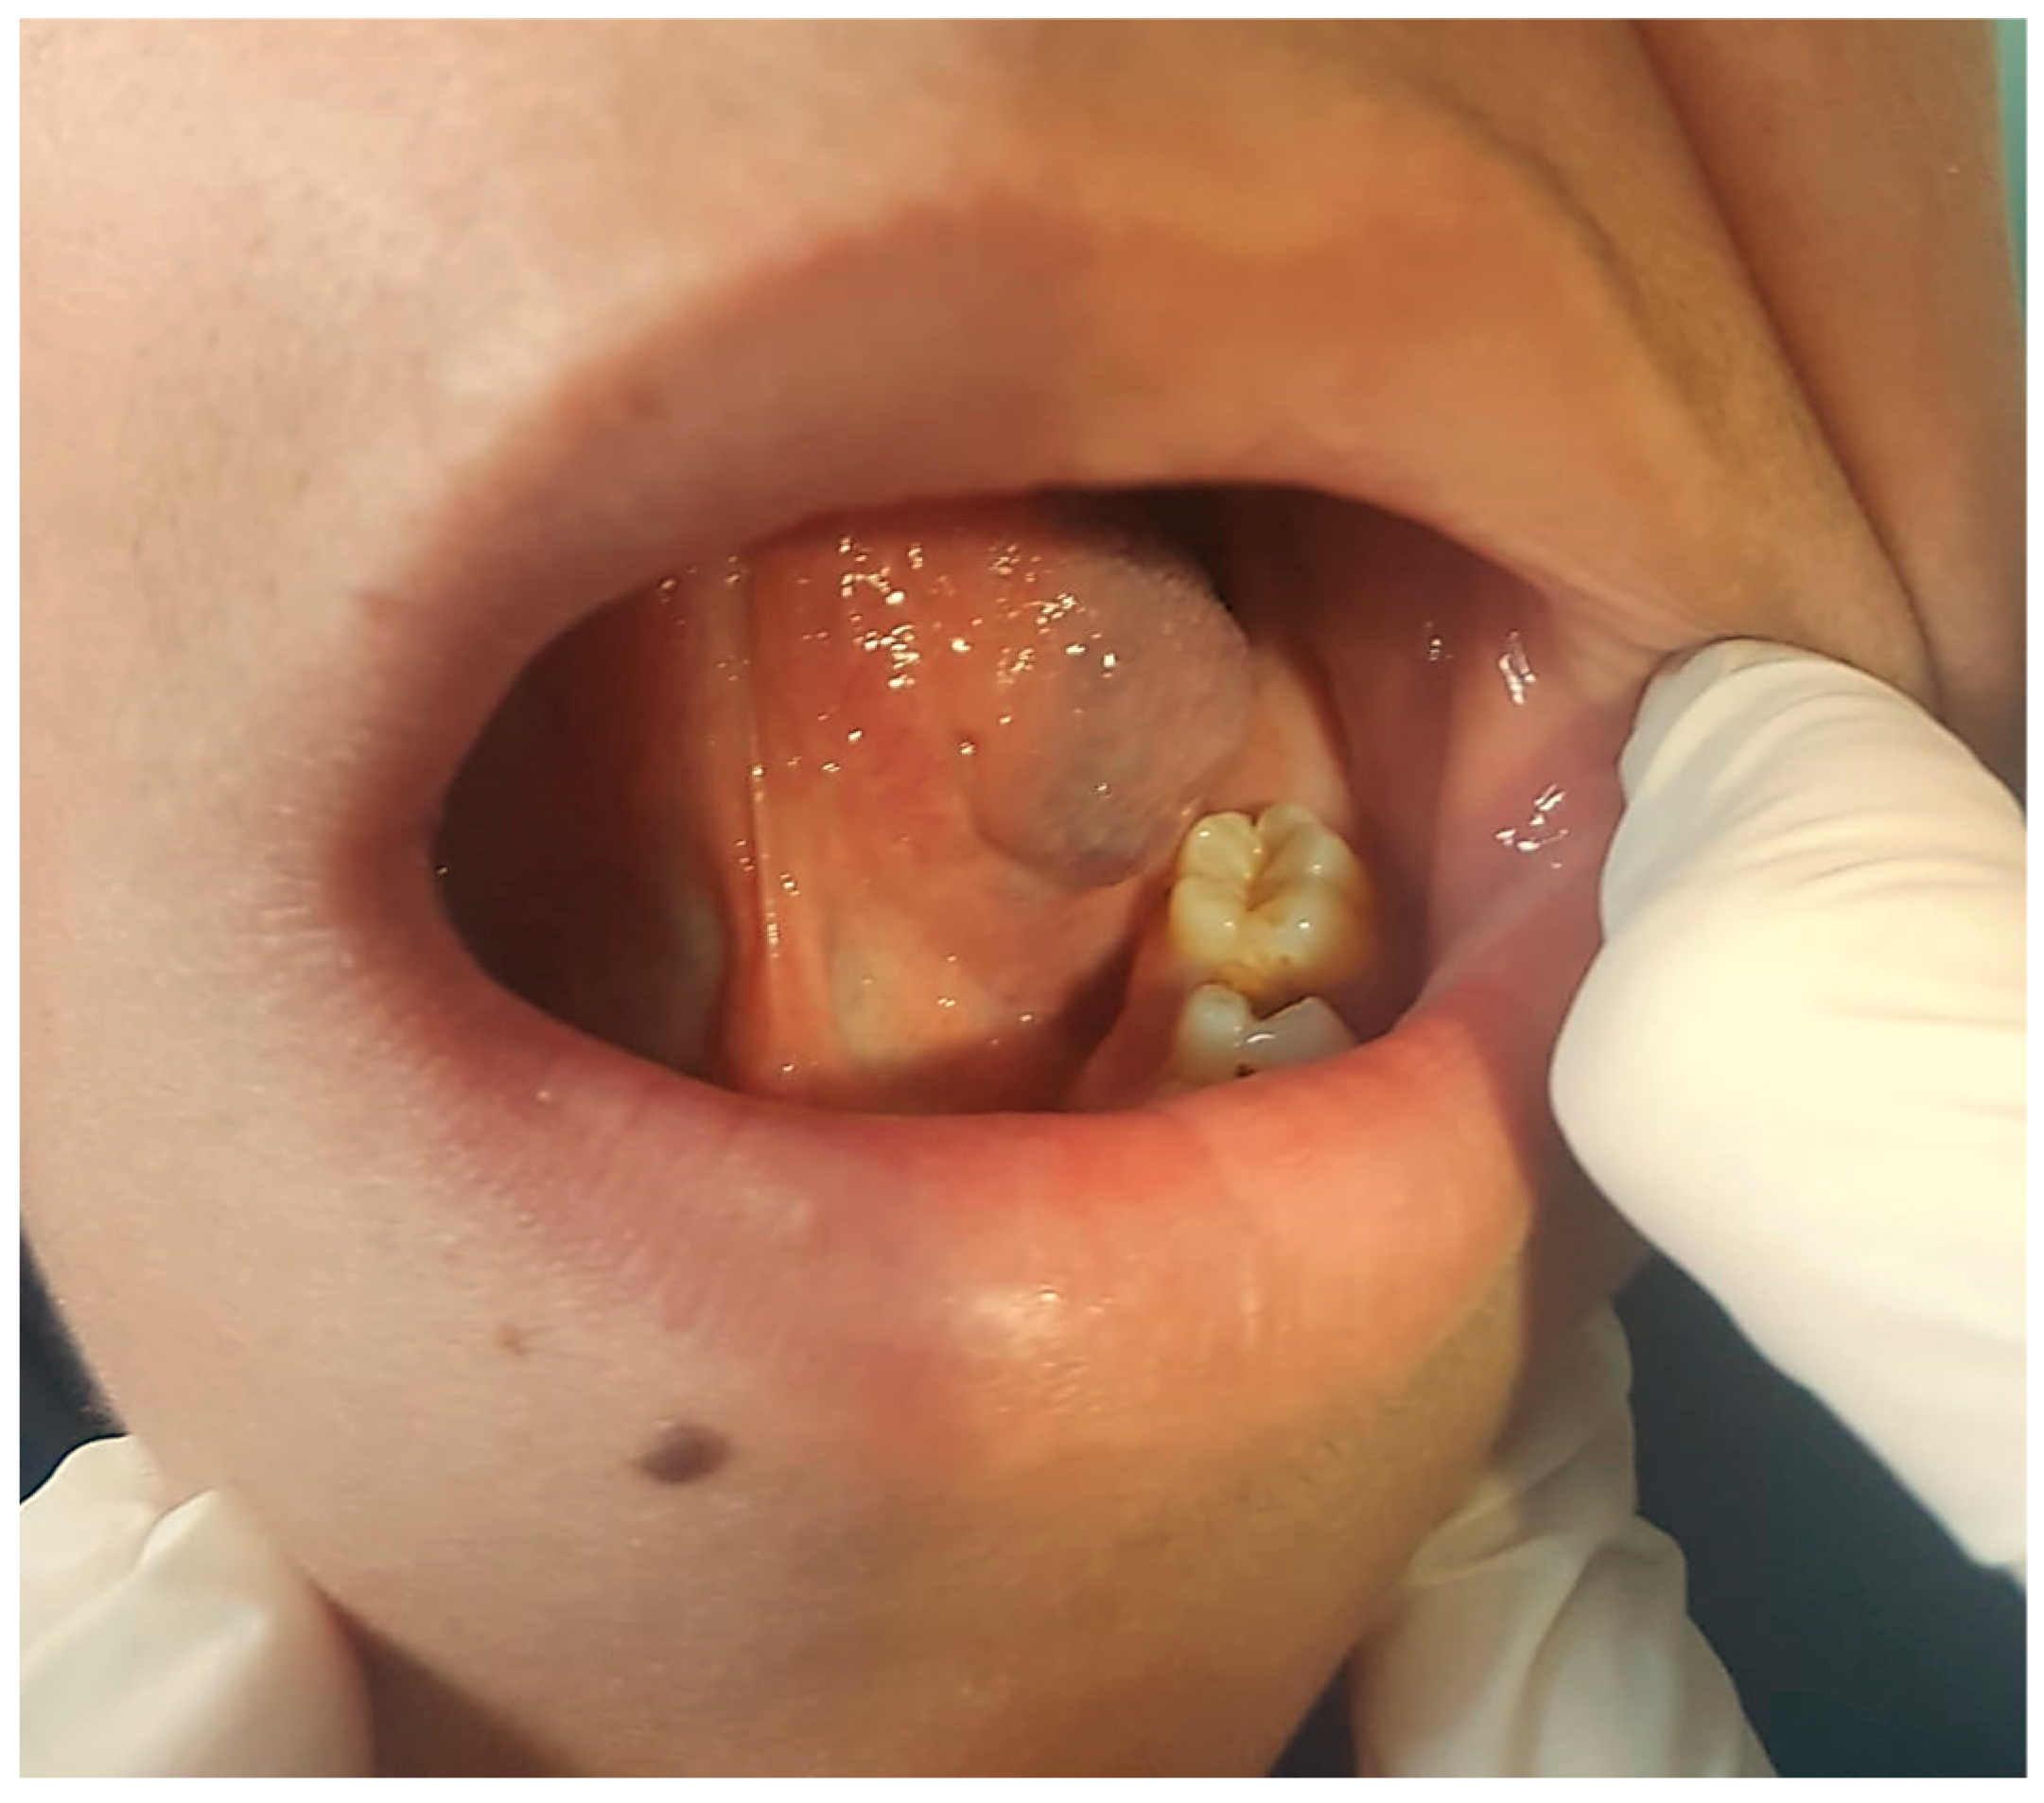

3.3.1. Clinical Data

3.3.2. Diagnosis